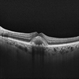

- maculoschisis, foveoschisis

Optical coherence tomography system

Zeiss Cirrus 6000 - Description

- HD 6x6 OCT-Angiography Structural View of the Deep Inner Retina